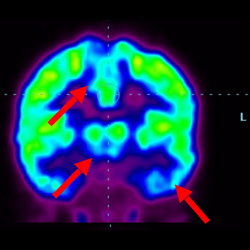

細(xì)胞治療前 PET CT 掃描顯示神經(jīng)組織中的藍(lán)/黑色區(qū)域,表明腦癱引起的大腦損傷。